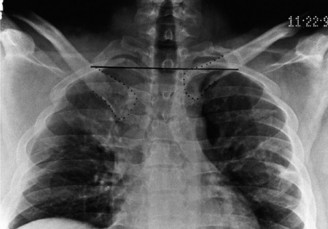

The correct answer is (A). The ED image shown in Figure 2–29 includes only an AP view of the right shoulder. In the setting of an acute injury and pain, technicians may be hesitant to obtain additional views. A single view, however, is insufficient to diagnose either a fracture, as orthogonal views are required, or a shoulder dislocation which is best seen on an axillary view (see Fig. 2–30). Answers B and C are inappropriate as a diagnosis has not been established yet and a dislocation or fracture must be conclusively ruled out. Answers D and E may be options that are exercised in the clinic but do not represent the next step in the management of this patient.

--- _Figure 2–30_A: Axillary view. B: Axillary view with annotations. Traumatic anterior instability is a common shoulder problem with an estimated incidence of 1.7%. This term encompasses both frank dislocations that require a manual reduction as well as incomplete subluxations that spontaneously reduce. It is particularly common in the young and athletic population, and it is significantly more common than other forms of instability including posterior or multidirectional instability. Understanding the natural history of anterior instability is important, as it serves as a guide to treatment. Young patients have a very high risk of recurrence; patients <20 years old have a 90% recurrence risk, between 20 and 40 years old have a 60% recurrence risk, and >40 years old have a 10% risk. Recurrent events are a predictor for arthritis and necessitate aggressive treatment, particularly in the young patient.